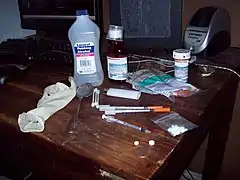

Drug injection is a method of introducing a drug into the bloodstream via a hollow hypodermic needle, which is pierced through the skin into the body (usually intravenously, but also at an intramuscular or subcutaneous, location). Intravenous therapy, a form of drug injection, is universally practiced in modernized medical care. As of 2004, there were 13.2 million people worldwide who self-administered injection drugs outside of medical supervision, of which 22% are from developed countries.[1]

In recreational-use drug culture, preparation may include mixing the powdered drug with water to create an aqueous solution, and then the solution is injected. This act is often colloquially referred to as "slamming", "shooting up", "smashing", "banging", "pinning", or "jacking-up", often depending on the specific drug subculture in which the term is used (e.g. heroin, cocaine, or methamphetamine).

The drug—usually (but not always) in a powder or crystal form—is dissolved in water, normally in a spoon, tin, bottle cap, the bottom of a soda can, or another metal container. Cylindrical metal containers—sometimes called "cookers"—are provided by needle exchange programs. Users draw the required amount of water into a syringe and squirt this over the drugs. The solution is then mixed and heated from below if necessary. Heating is used mainly with heroin (though not always, depending on the type of heroin),[4] but is also often used with other drugs, especially crushed tablets. Cocaine HCl (powdered cocaine) dissolves quite easily without heat. Heroin prepared for the European market is insoluble in water and usually requires the addition of an acid such as citric acid or ascorbic acid (Vitamin C) powder to dissolve the drug. Due to the dangers from using lemon juice or vinegar to acidify the solution, packets of citric acid and Vitamin C powder are available at needle exchanges in Europe. In the U.S., vinegar and lemon juice are used to shoot crack cocaine. The acids convert the water-insoluble cocaine base in crack to a cocaine salt (cocaine acetate or cocaine citrate), which is water-soluble (like cocaine hydrochloride).

Once the drugs are dissolved, a small syringe (usually 0.5 or 1 cc) is used to draw the solution through a filter, usually cotton from a cigarette filter or cotton swab (cotton bud). "Tuberculin" syringes and types of syringes used to inject insulin are commonly used. Commonly used syringes usually have a built-in 28 gauge (or thereabouts) needle typically 1/2 or 5/8 inches long.